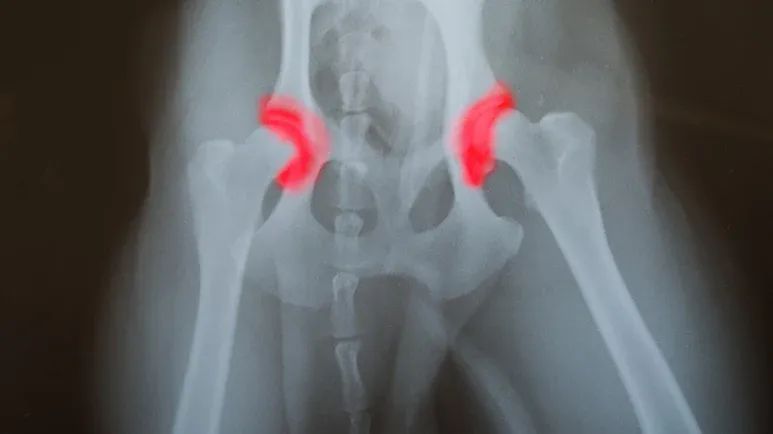

A dog is diagnosed with CHD if the ball and socket hip joint is malformed, causing separation of the two bones of the joint. In most cases, the socket is not deep enough for the ball to fit snugly into place.

In a dog with healthy hips, the ball (the head of the femur) at the top of the leg bone fits perfectly into the socket. In animals with CHD, the less-than-perfect fit causes the bones to separate. This separation is the result of abnormal joint structure coupled with weak muscles, ligaments, and connective tissue that support the joints.

The result is a joint that chafes and grinds rather than slides smoothly during movement. Often the body tries to compensate for the poorly fitting joint by producing hard, bony material in and around it in an attempt to stabilize it. This alteration can have the opposite effect, creating an even more unnatural fit.

If your pet is symptomatic, there will be signs of mobility problems and pain. The vet will perform a complete physical exam and take x-rays. Problems with a joint are often easily seen on x-rays of dogs exhibiting symptoms. Your vet may also be able to feel looseness in your dog’s hip joint, and note pain when a rear leg is extended or flexed.